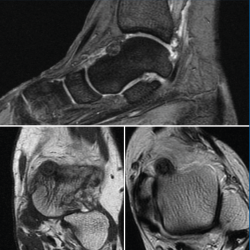

Se trata de una mujer de 64 años que presenta dolor en el tobillo izquierdo de 36 meses de evolución; la paciente refiere un dolor nocturno para el que precisa toma de salicilatos. Se realizó una radiografía que no evidenció lesiones óseas, la TAC nos informa de una lesión lítica yuxtacortical en el astrágalo de 8 mm de diámetro con calcificaciones de aspecto condroide en el centro de la misma (Figura 1). La RMN sugería un OO, ya que presentaba una tumoración ósea en el cuello del astrágalo con cambios inflamatorios periféricos y abundante edema óseo difuso del astrágalo (Figura 2).

Figura 2. Resonancia magnética nuclear inicial que presenta una tumoración ósea en el cuello del astrágalo con cambios inflamatorios periféricos y abundante edema óseo difuso, sugestivo de osteoma osteoide.